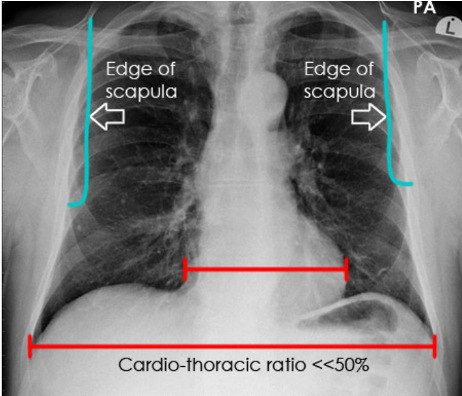

What is the normal cardio-thoracic ratio in a PA CXR?

A

<0.5/50%

What is a healthy heart size on a CXR?

Heart should occupy no more than **50%** of the thoracic width (e.g. a cardiothoracic ration of \<0.5). Note - This rule applies only to PA CXRs (as AP films exaggerate heart size).

58

What defines cardiomegaly on a CXR

If the heart occupies \>50% of the thoracic width on a PA CXR